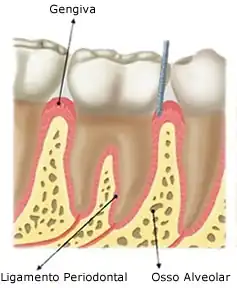

A arcada alveolar é a porção da maxila e da mandíbula que forma e suporta os alvéolos dentários. É formado quando o dente erupciona para promover inserção óssea para o ligamento periodontal em formação; quando o dente é perdido, desaparece gradualmente.

A arcada alveolar é contido de osso alveolar que reveste os alvéolos. Ele é composto de uma fina lâmina de osso cortical, com numerosas perfurações, que permitem a passagem de vasos sanguíneos entre os espaços medulares do osso e ligamento periodontal. A margem coronal do osso alveolar forma a crista alveolar, que geralmente está paralela à junção cemento-esmalte em uma distância de 1-2 mm para apical. O processo alveolar é o maior responsável pelo crescimento vertical da maxila, onde a maior deposição óssea ocorre no seu bordo inferior.